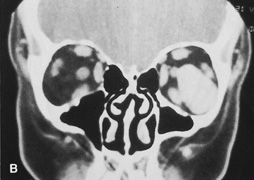

Valuable information about the nature and extent of an orbital pathologic process is provided by imaging studies such as computed tomography (CT) scan, magnetic resonance imaging (MRI), and orbital echography. Better spatial resolution, ready accessibility, and lower cost make CT the preferred choice for orbital imaging in most cases. Orbital fat provides a natural contrast between most adjacent orbital structures on CT scanning, and orbital bones are visualized well. Computed tomography is essential for evaluation of the orbital bones because they cannot be imaged with MRI. Direct coronal or sagittal images are important to identify the relationship of a lesion to the optic nerve so that the surgical approach can be planned to avoid traversing the optic nerve (Fig. 1).

Fig. 1. A. Axial CT scan demonstrating a large, well-encapsulated lesion in the orbital apex. Coronal (B) and sagittal (C) scans demonstrate that the mass lies inferior and medial to the optic nerve within the intraconal space. This information is useful in planning the surgical approach to the mass, which should avoid traversing the optic nerve.